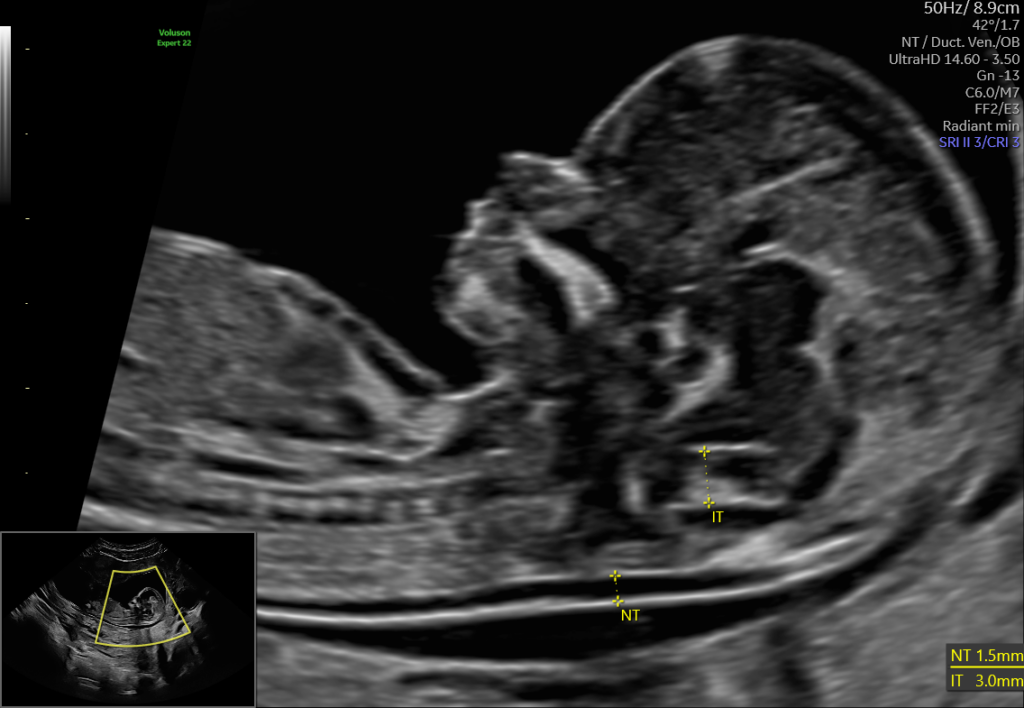

NT-Prawidlowy-obraz-przeziernosci-karkowej-plodu-grubosci-15-mm-w-13-tyg.png

Zwiększona przezierność karkowa bez innych nieprawidłowości

Kluczowe znaczenie ma to, czy zwiększona NT występuje izolowanie, czy towarzyszą jej inne odchylenia.

Jeśli:

• zwiększona przezierność karkowa jest jedyną nieprawidłowością,

• pozostałe parametry są prawidłowe,

• kolejne badania (15–18 tydzień oraz badanie połówkowe) nie wykazują wad,

➡️ ryzyko poważnej choroby istotnie spada.

Dla pacjentki jest to bardzo silny sygnał uspokajający.